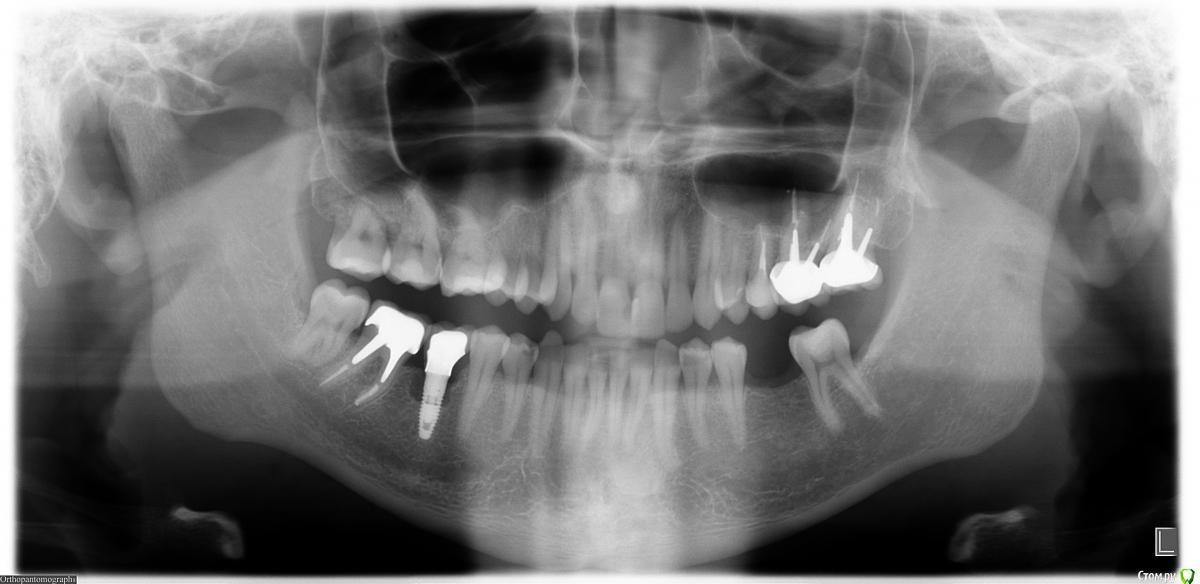

stoma Опубликовано 21 декабря, 2015 Поделиться Опубликовано 21 декабря, 2015 Добрый день!Возник периимплантит в установленном ~ 6 лет назад импланте.Сейчас слегка отечна десна около него (это и был повод обращения в клинику).Снимок прикрепляю.Врач предложил 2 варианта - лечить (чистка + подсыпка костного мат-ла или удалять, а через 6-8 мес. заново ставить).Как быть? Ссылка на комментарий

diesel87 Опубликовано 21 декабря, 2015 Поделиться Опубликовано 21 декабря, 2015 Я бы удалил, половина высоты кости потеряна, лечение не факт что даст долгосрочного положительного результата. Можно и через 4-6 мес повторно поставить. 1 Ссылка на комментарий